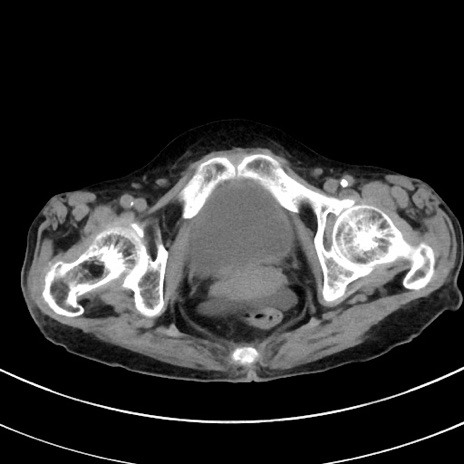

症例33(横断像)

【症例】70歳代 女性

【主訴】心窩部痛

【現病歴】延髄病変の精査・加療にて神経内科入院中。本日より心窩部痛あり。

【既往歴】虫垂炎

【身体所見】右下腹部を中心に圧痛と反跳痛あり。

【データ】WBC 10900、CRP 0.02